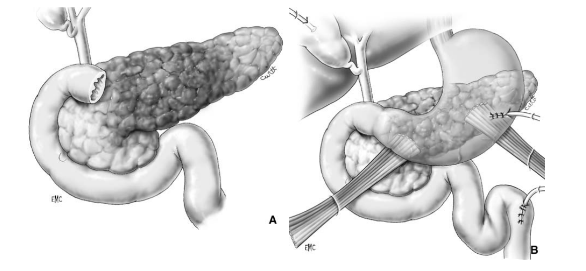

Phẫu thuật Patch tá tràng – Patch technique

A – Tổn thương rộng ở D2, lộ bóng Vater

B – Đưa quai hỗng tràng lên úp vào vết thương D2 kiểu Roux-en-Y

Phẫu thuật cắt bỏ một phần tá tràng

A- Vỡ D3 độ III (AAST) ngay sát bó mạch mạc treo tràng trên

B- Cắt đoạn D4, nối hỗng tràng với D2 Roux-en-Y